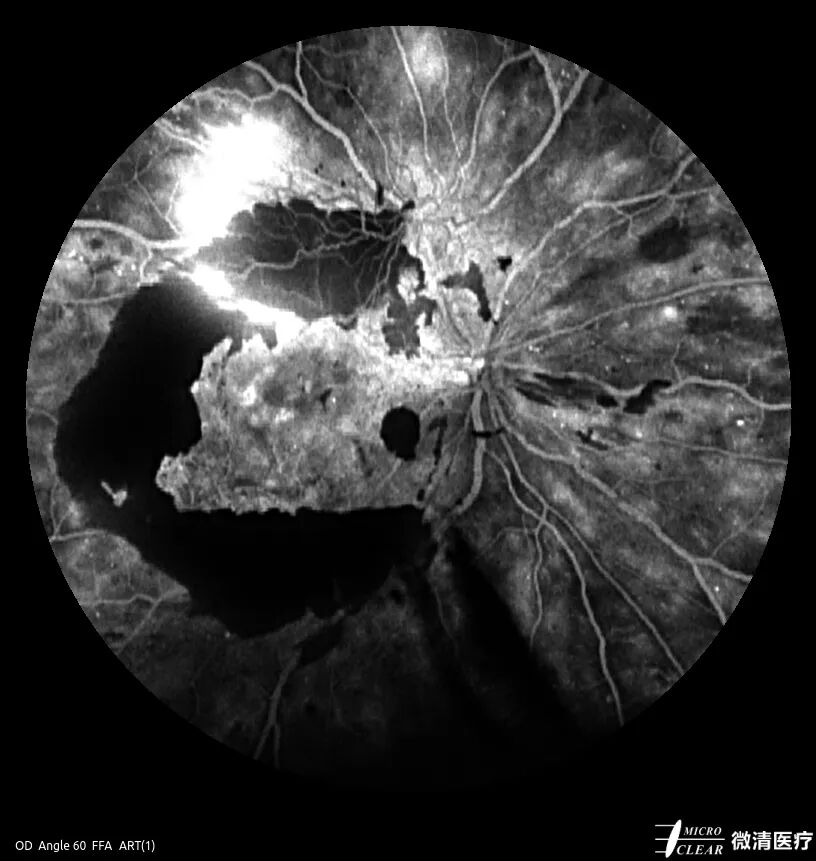

充盈异常:包括充盈缺损、充盈迟缓、逆行充盈,常见于糖尿病性视网膜病变(无灌注区)、视网膜中央动脉阻塞、视网膜静脉阻塞等。

糖尿病性视网膜病变无灌注区(左)、视网膜中央动脉阻塞(右)